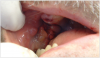

Patients typically present with a sore throat, ear pain, painful swallowing, or hoarseness, and on physical exam they often have lymph node involvement in the neck. The highest risk sites are at the base of the tongue and the tonsillar area. Palpation of the neck has never been more important. The highest frequency of HPV-positive cancer is related to oral sex and to the number of partners. Figure 2 shows an example of cancer, found on the buccal mucosa.

Figure 2. Example of Oral Cancer - courtesy of dentalcare.com

Figure 2